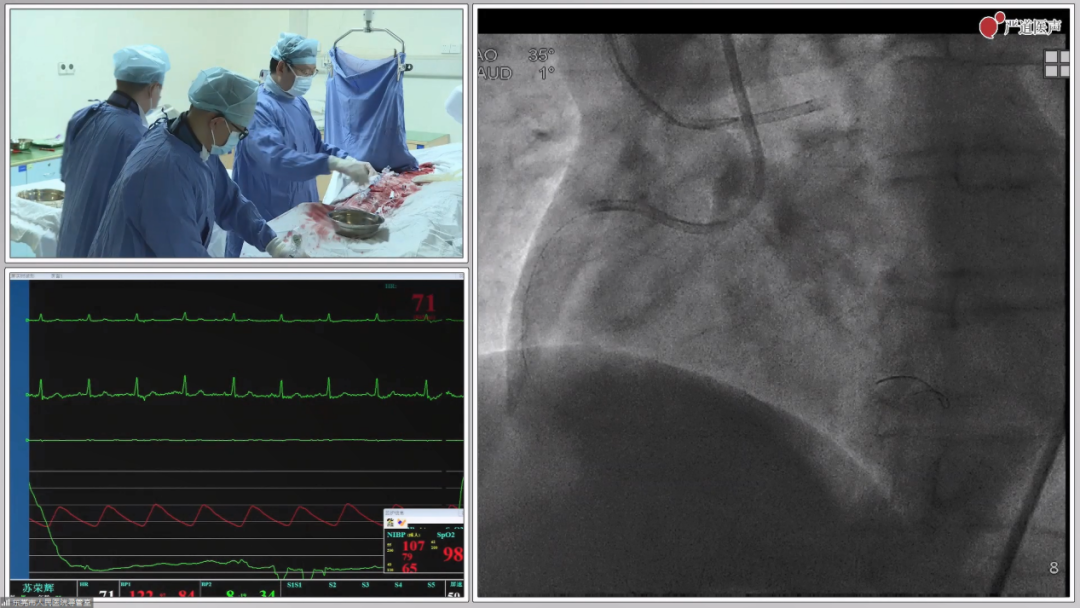

在了解了第二台手术手术的难度之后,在场专家表示,和第二台相比,第一台的手术只能算是小试牛刀。本台手术为一个65岁男性患者,患者平时走路100米即可出现胸闷症状,造影显示患者冠脉三支病变,合并左主干弥漫性狭窄,患者前降支回旋支闭塞,右冠状动脉中段狭窄约95%,上次造影时已经开通右冠状动脉并处理左主干病变,但是前降支及回旋支仍未处理,此次东莞市人民医院希望张教授能够开通患者的剩余血管。张教授在观看了上次造影过程后,还是决定给患者开通CTO病变,改善患者症状及预后,在经过3个多小时的不懈努力后,最终成功开通CTO病变,植入Resolute Integrity 长支架(34mm)一枚,患者症状得到了极大缓解。

本例手术是一个冠脉三支病变患者,患者三个月前因胸痛就诊于东莞市人民医院,造影显示前降支重度狭窄,回旋支、右冠慢性闭塞,后处理前降支病变,剩余回旋支、右冠状动脉闭塞未处理。患者基本情况较差,心功能1级,既往曾患脑梗。肖践明教授根据患者情况分析指出该患者RCA-CTO有残存的微通道,可以依靠同侧造影的指引、微导管的支撑从而通过病变,而LCX-CTO无残存的微通道,且存在10mm的闭塞段,因此选择合适的CTO导丝以及导丝穿刺方向尤为重要。在肖教授的指导下,郭素峡、黄志超主任成功将导丝穿过病变处,并释放支架。

在面对普通狭窄病变时,很多医生都可以顺利植入支架,而对于长狭窄病变,如何将支架放对位置则需要考验术者的操作水平。在今日展示的病例中,张新金教授面对的就是一例长狭窄病变,该患者患有冠脉三支病变,于一周前成功处理前降支及回旋支病变,但是剩余右冠状动脉严重狭窄伴弥漫长病变未处理,张教授在了解了患者基本情况后指出该患者病情较复杂,虽然上次手术已经开通前降支及回旋支血管,但是患者右冠状动脉弥漫性狭窄,狭窄程度严重且病变较长,患者一般情况差,射血分数减少,开通右冠状动脉很有必要,但是弥漫长病变如何将支架放对位置很重要。根据张教授的指导,郭素峡主任成功将导丝送入狭窄病变远端并植入支架,Normal to Normal原则完美 。